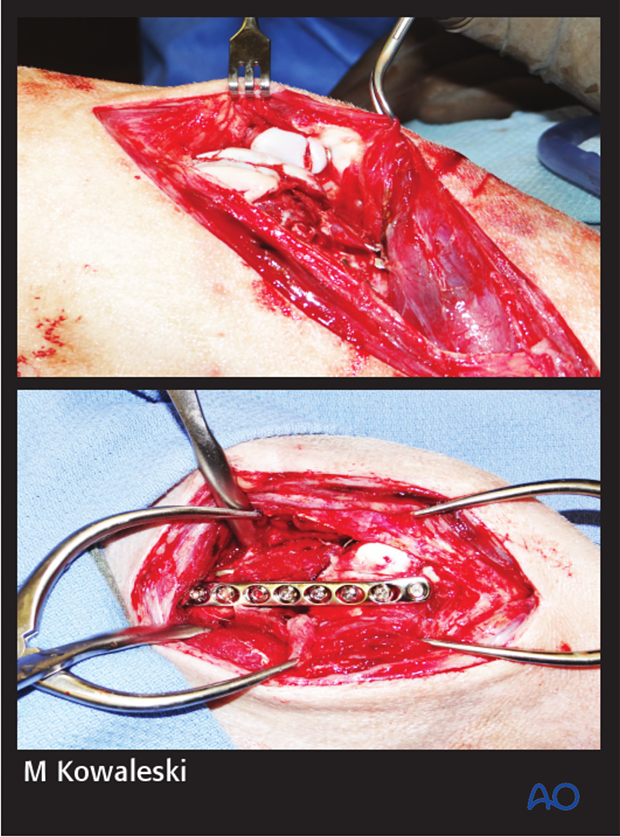

The fracture was approached initially through a lateral parapatellar approach and the articular fractures were visible.

The articular fractures were repaired first using a combination of smooth pins and screws. The implants were countersunk below the articular surface.

A lateral parapatellar arthrotomy was then performed for repair of the patellar fracture with a pin and tension band fixation and bridging plate application on the distal femur with a LC-DCP.